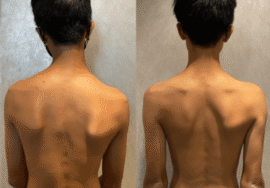

اعوجاج العمود الفقري عند الأطفال والمراهقين هو من أكثر المشكلات التي تثير قلق الأهالي، خصوصًا عندما يخبرهم الطبيب أن الانحناء قد يزداد مع الوقت إذا لم تتم متابعته أو علاجه بالشكل الصحيح. ولهذا يبحث الكثير من الأهالي عن إجابة واضحة لسؤال مهم: ما الذي يمكن أن يجعل اعوجاج العمود الفقري يسوء؟

السبب الرئيسي لزيادة الانحناء هو النمو السريع. فعندما يدخل الطفل أو المراهق مرحلة النمو، خصوصًا بين عمر 10 و15 سنة، يبدأ العمود الفقري في التمدد بسرعة، وهنا يمكن أن يتفاقم الانحناء إذا لم تتم المتابعة الصحيحة.

الأطفال قد لا يشتكون كثيرًا، لكن هناك علامات يجب ألا يتجاهلها الأهل:

بروز الضلوع

ارتفاع كتف عن الآخر

ميل الحوض

عدم انتظام الخصر

ألم متكرر في الظهر

هذه قد تكون إشارات على زيادة زاوية الانحناء، ويجب مراجعة الطبيب فورًا.